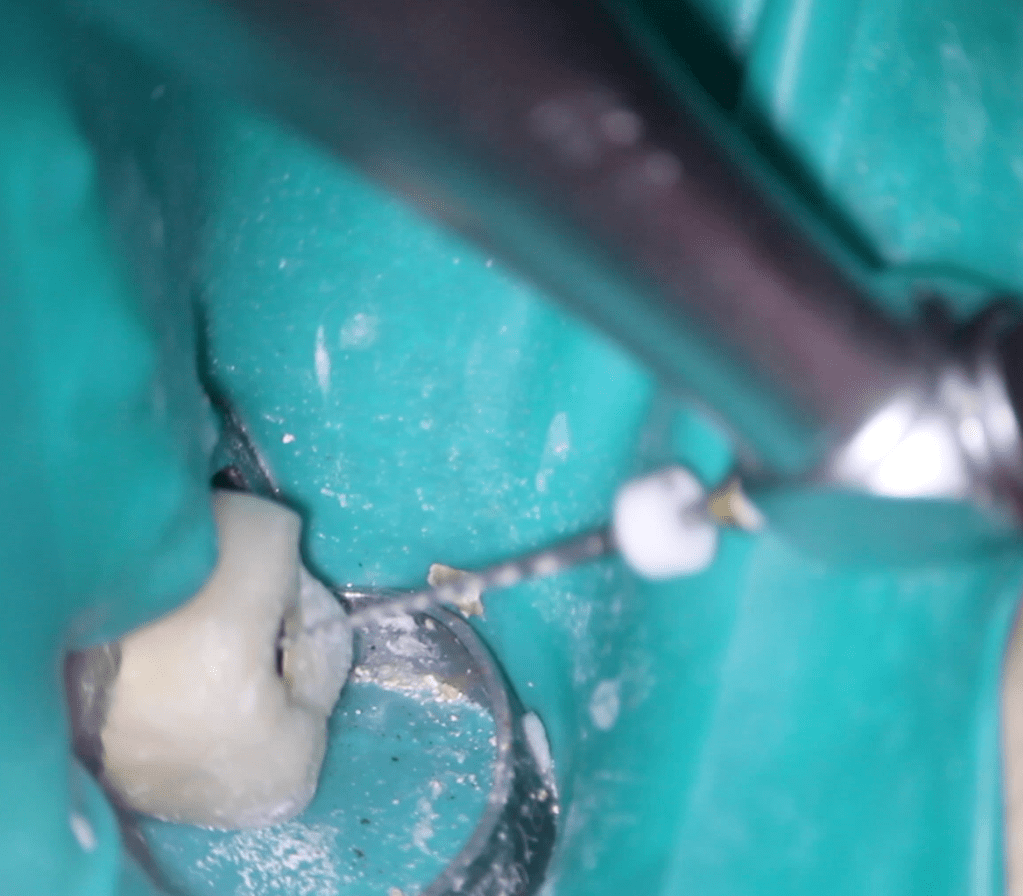

Reconstrucción preendodóntica

Gingivectomía +reco preendo +reconstrucción

Molar superior

Reco palatina

Reco pared vesticular

Reco pre-endo gingivectomái, pared yuxtaosea

Reco pre-endo, molar inferior

Reco preendo + 4 conductos molar superior

Reco preendo + gingivectomía

Reco preendo, 2o Molar superior

Reconstrucción debajo de puente